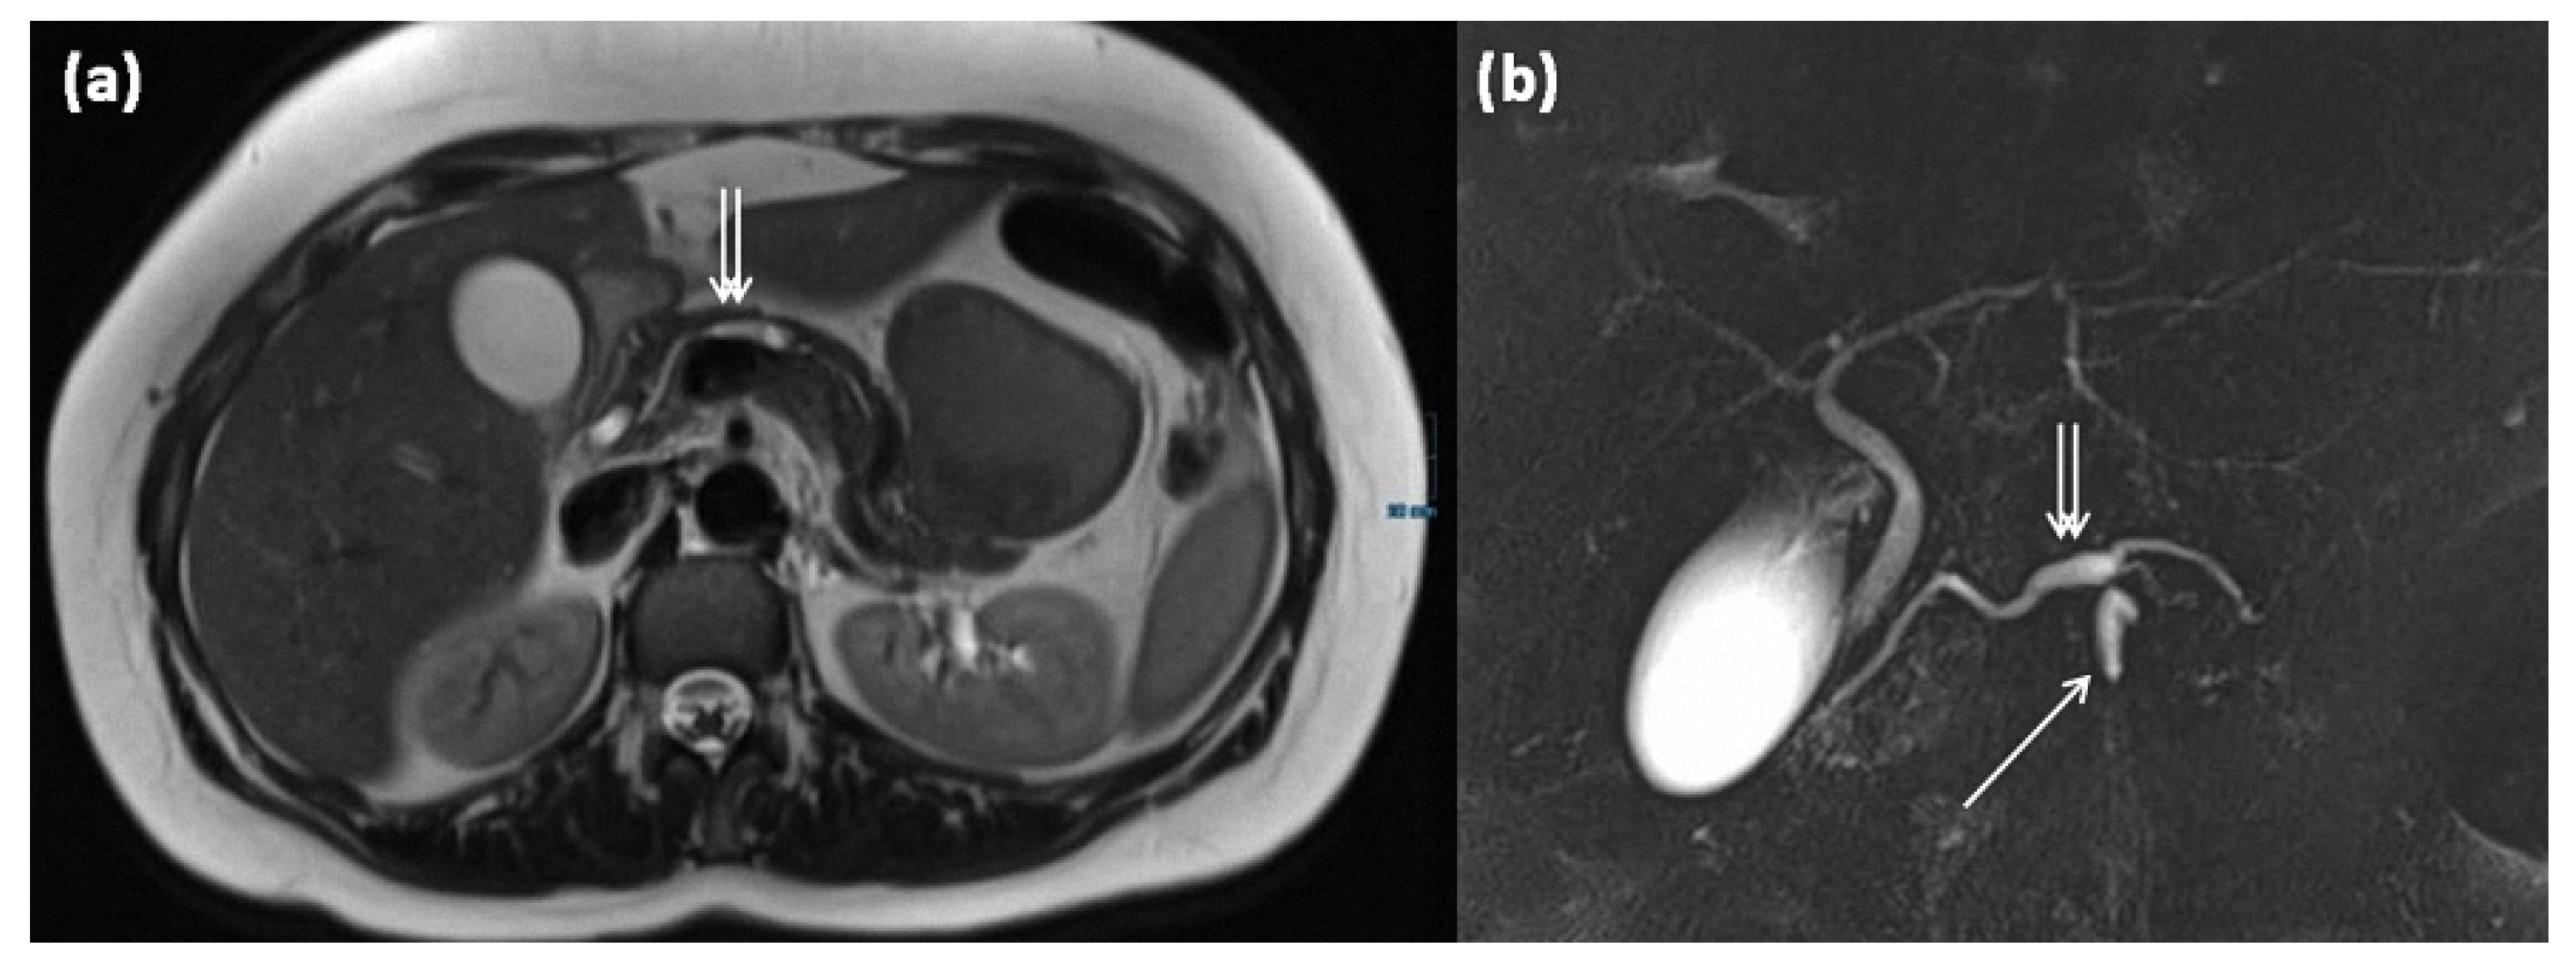

Figure 15.

MRI of a 39-year-old female patient with T2w (a) and magnetic resonance cholangiopancreaticography (MRCP) (b). Images show a clear demarcated main duct dilatation in terms of a main duct IPMN (double arrow). Furthermore, the extension of a branch duct (arrow) can be seen, thus of a combined main and branch duct IPMN is present (mixed-type).